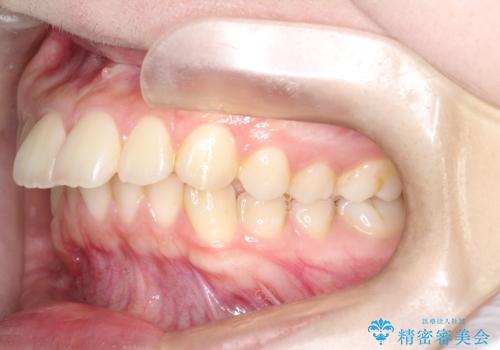

- 前歯が出ている事を主訴に来院されました。

上と下の前歯がずれているため、抜歯を行い前歯の真ん中を合わせる治療計画を立ててワイヤー矯正にて治療を行いました。